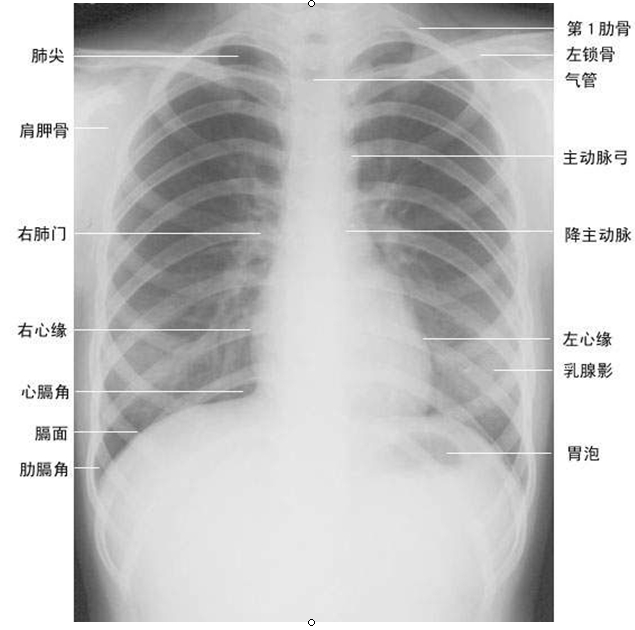

胸部X线片系统读片原理

A(Airway)气道在胸上部,看它是否居中,脊柱是否直线经过,气管有无移位,有无纤维组织牵拉使肺容积缩牵、过度充气及压迫。有无支气管气管巨大症,肺叶开口压迫、狭窄、隆突受压等支气管肺癌征象。

B(Bone)肋骨距是否某侧缩窄,肋骨有无缺损,如第一肋骨上缘缺损,有硬皮病、类风湿性关节炎的可能。第7~9肋骨下缘缺损示主动脉狭窄,见于儿童先天心脏病;法乐氏四联症可见左肋下缘缺损。咳嗽所致骨折,可见于6~9肋,第7肋腋后线可见叉形肋。鸽胸与先天性房室间隔缺损相关,也见于儿童哮喘症或脊柱侧凸严重时伴通气功能降低者。骨脱钙可见于类固醇治疗患者、老年、肾病、或其他代谢病者。

C(Cor)心脏右缘有两弓,左缘有四弓。右两弓消失见于漏斗胸、右中叶萎缩、肺炎。形状变化或心脏扩大,见于先天性心脏病、心力衰竭。

D(Diaphragm)膈肌右高于左半个肋间隙,一侧高,考虑胸部肿瘤、纤维组织牵拉、膈下脓肿。半侧膈肌升高考虑外伤、中风、颈部感染或肿瘤、肺炎或放射治疗后。右侧可见膈肌伴弯刀征。医 学.教育 网原 。创

E(Esophagus)食管位于气管右,若有空气液面,考虑食管不能松驰或狭窄。

F(Fissures)肺裂将各肺分为各叶,左右各有一斜裂,右侧有横裂,斜裂下端止于膈肌,决不止于前胸壁,有异常时示有病变。

G(Gastric bubble)胃泡在左侧,若在右,考虑内脏转位,胃泡不见,考虑食管不能松驰。胃泡在心右可能为膈疝。

H(Hila)肺门移位示肺部分萎缩、过度充气等,肺门区扩大可能是肺癌转移、肺内感染、免疫疾病或结节病。

以上24个字母,便于记忆,可全面观察胸片各个解剖部位的结构的正常与异常阴影,借以了解病变特点,得出诊断。